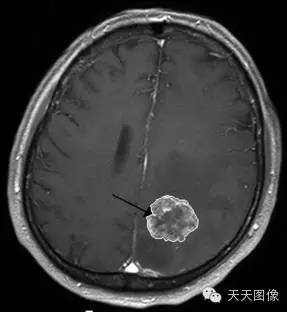

下面只上几张比较中规中矩的肿瘤图像。

上面是一些典型的脑肿瘤图,图中的白块就是肿瘤。为了让大家看的更直观,特地选出来一些比较好分割的图像,但是也并不是什么方法都能分割出来的,就我个人知识而言,不进行任何预处理,没有一种方法可以自动地直接将这些肿瘤都给分割出来。不信可以去问问周边搞图像的人,如果有,请务必告诉我。

下面是我的分割结果,算不上完全自动,但是也是基本上不需要监督。(仔细看肿瘤周围叠加的轮廓,就是分割的结果)

用到的方法就是水平集。